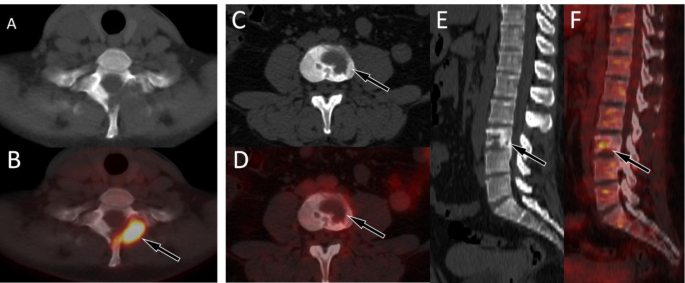

Our current study enrolled a total of 10 LCH patients with spinal involvement, with a median age of 26 years old, which differs from the literature reporting that LCH is more common in children. This may be related to our inclusion of only LCH patients with spinal lesions. The epicenter of the lesions are located in the vertebral body and usually present as osteolytic destruction with incomplete bone cortex, while less causing vertebral compression. Lesions in the active phase typically do not have sclerotic rims and significantly increased 18F-FDG uptake (Fig. 4A, B). However, lesions in the stable phase are the opposite, usually accompanied by sclerotic rims and mildly increased 18F-FDG uptake (Fig. 4C–E). It is worth mentioning that none of the spinal LCH patients enrolled in our study had lesions compressing the spinal cord, which is inconsistent with what has been reported in the above literature21.

(A,B) A 37-year-old woman with LCH; (A) Axial CT reveals low-density osteolytic bone destruction shadow on the left vertebral plate of the first thoracic vertebra, without sclerotic rims (arrow); (B) The PET/CT fusion image of the corresponding area shows obviously increased 18F-FDG uptake (arrow), with a SUVmax of 8.9, suggesting that the lesion is in an active phase. (C–F) A 23-year-old woman with LCH; (C), Axial CT revealed low-density osteolytic bone destruction in the third lumbar vertebrae (arrow), without the formation of soft tissue masses; (D), The PET/CT fusion image of the corresponding area shows mildly increased 18F-FDG uptake (arrow), with a SUVmax of 3.5; and sagittal images (E CT; F PET/CT) revealed lesions with osteosclerotic rims (arrows), suggesting that the lesion may be in remission. LCH = langerhans cell histiocytosis.